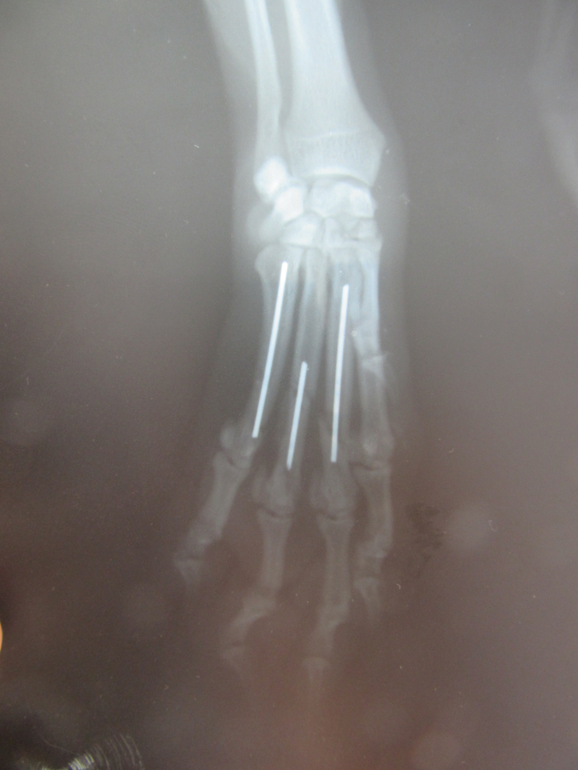

Полный перелом 3,4,5 пястных костей со смещением передней лапы у собаки

Перелом случился по вине моей и мужа,понятно было сразу,что лапе п.здец,собака очень плакала.Сразу же муж повез Варю в ветеринарку,откуда его направили на рентген на Кр.Путь 139 б клиника "Биота".Сделав снимок выдали заключение "Полный перелом 3,4,5 пястных костей со смещением передней левой лапы".Время шло к закрытию.Муж шокирован,ему что-то обьясняют врачи,он сказал что мало что понимал от состояния своего.Сказали сразу-операция,стоимость 10 т.р.Сутки на подумать.Не понимаю почему муж сразу же не записался на операцию,меня не было с ним.Пока он ехал я обзванивала беспощадно закрывающиеся ветклиники......Многие этим не занимаются,а другие говорят "Приходите,консультация 500 р,а там будем решать гипс или операция".ШТЭ???????????Какой нахер гипс,бля?????????Бегите из клинике,если озвучив такой диагноз вам говорят про гипс!!!!Собака лежала весь вечер и всю ночь на месте,передвигалась по надобности на 3 лапах.Я твердо решила,что врачи в клинике Биота адекватные,вынесли верное решение,вставлять штифты.

Фото что было и что стало.

Теперь Варюшка -Россомаха!Удачного нам заживления)